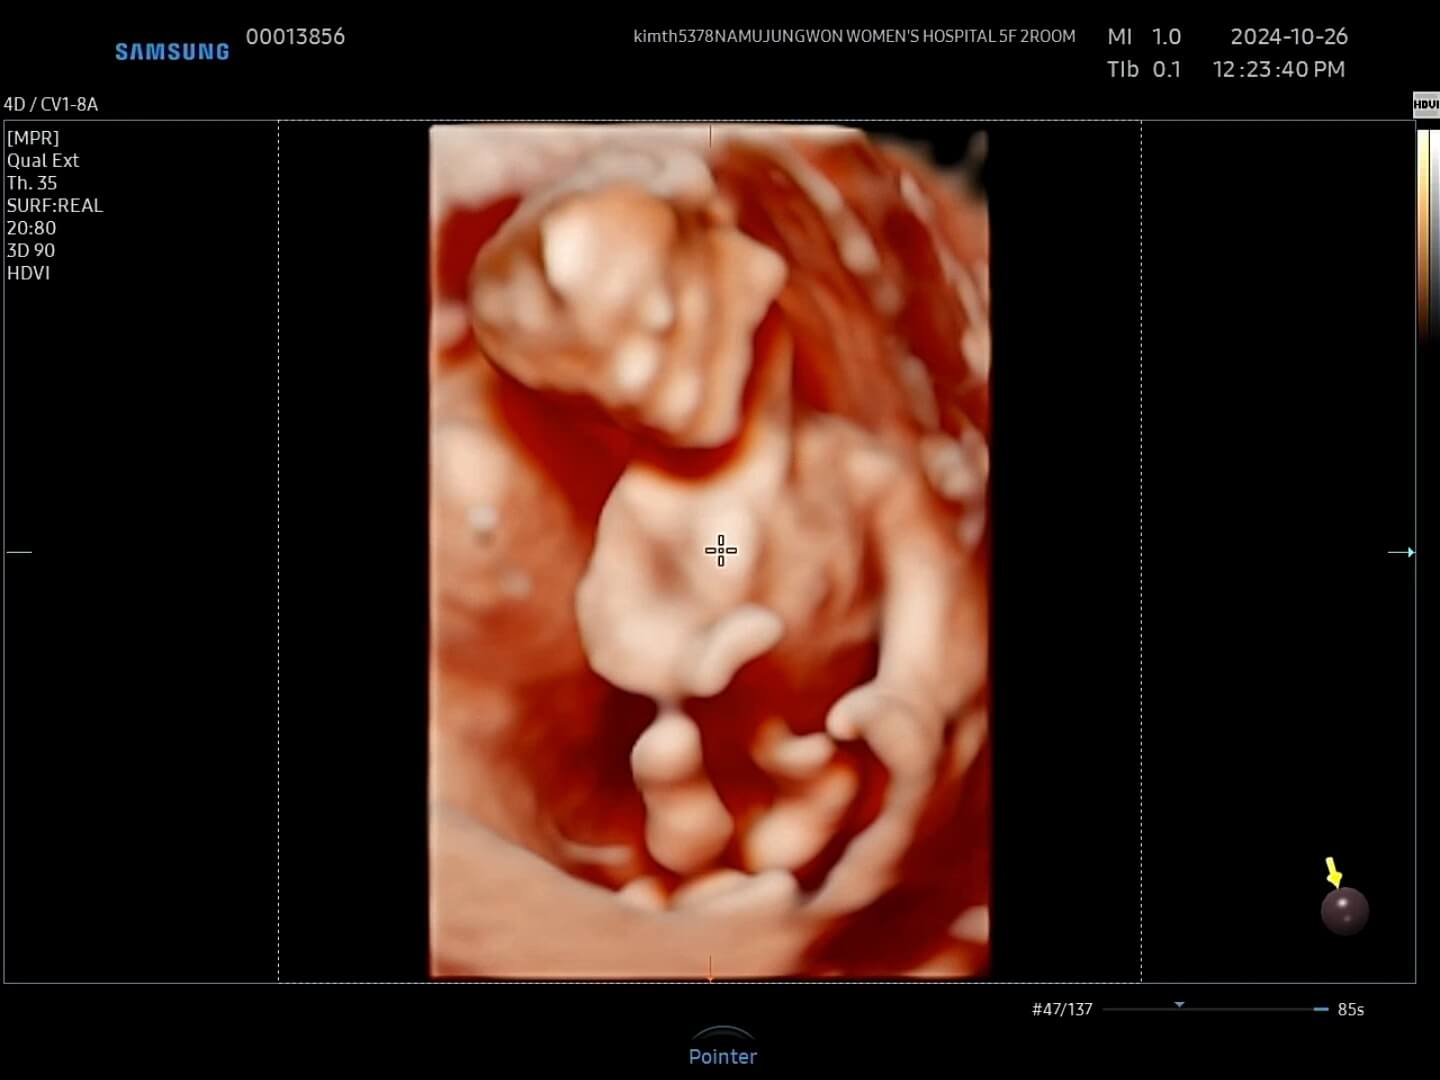

4. 12주 입체초음파

드디어 12주가 되어 꾸미의 첫 입체초음파를 보는 날이 되었어요! 두근두근, 꾸미는 얼마나 커있을까요?

12주-입체초음파 12주에는 첫 입체초음파를 보게 되면서 팔, 다리가 잘 형성되었는지 정도를 보는 것 같아요. 12주부터 '태아'라고 부르기도 한답니다. 우리 꾸미는 처음에는 등을 돌리고 있다가 서서히 얼굴을 보여줬습니다. 벌써부터 귀여워요! 아들인지 딸인지 너무 궁금했는데요, 성별은 입체 초음파가 아닌 일반 초음파로 봐야한다고 하셨어요.